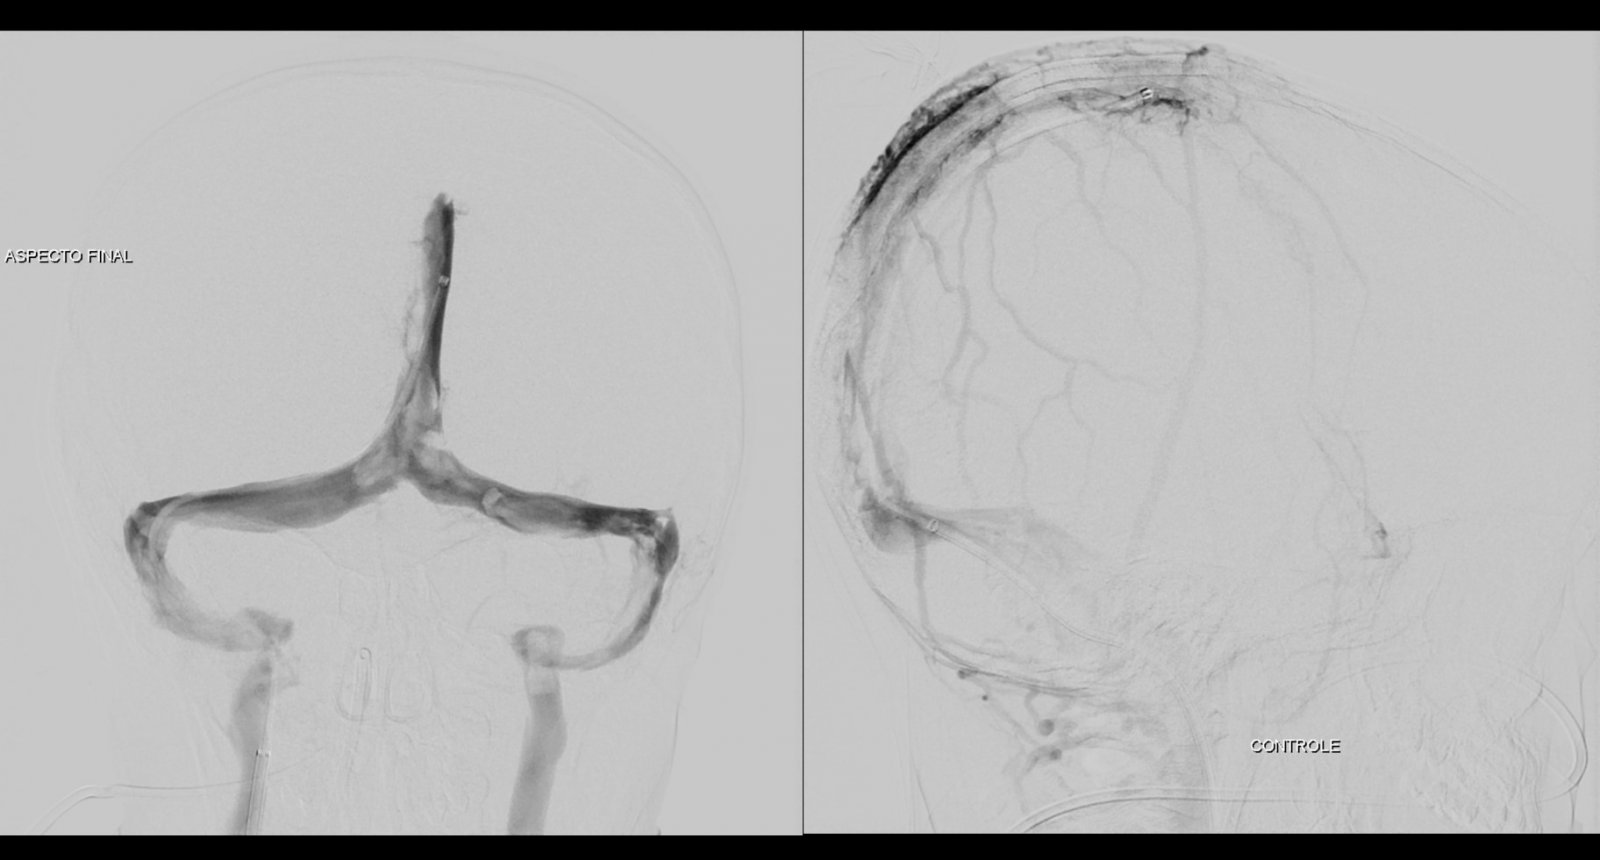

Paciente é extubado em sala e encaminhado a UTI pediátrica. Após 24 horas, apresenta melhora da força em hemicorpo esquerdo e a mãe relata melhora da sonolência, chorando com mobilização do paciente. Sem sinais de complicações no local de punção.

O caso clínico apresenta a utilização de materiais com finalidades primárias para trombectomia mecânica no contexto de acidente vascular cerebral (Rebar 27 + Solitaire) e o balão Copernic RC (Balt) comumente utilizado auxiliando na embolização de fístulas durais para os seios, auxiliando no processo de trombectomia mecânica no contexto de extensa trombose venosa cerebral.